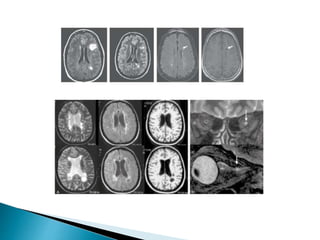

 Características de las lesiones

desmielinizantes en 95% de los casos:

◦ Hipointensas T1.

◦ Hiperintensas T2.

◦ Ovoides / forma de anillo abierto.

◦ Diámetro de 3 a 6 mm.

◦ Bordes brumosos mal definidos.

◦ Reforzamiento en T1 GDTPA.

 Características delas lesiones desmielinizantes en 95% de los casos: ◦ Hipointensas T1. ◦ Hiperintensas T2. ◦ Ovoides / forma de anillo abierto. ◦ Diámetro de 3 a 6 mm. ◦ Bordes brumosos mal definidos. ◦ Reforzamiento en T1 GDTPA. Enfermedades desmielinizantes del sistema nervioso central O. Fernández, V. E. Fernández y M. Guerrero - Medicine. 2015;11(77):4601-9